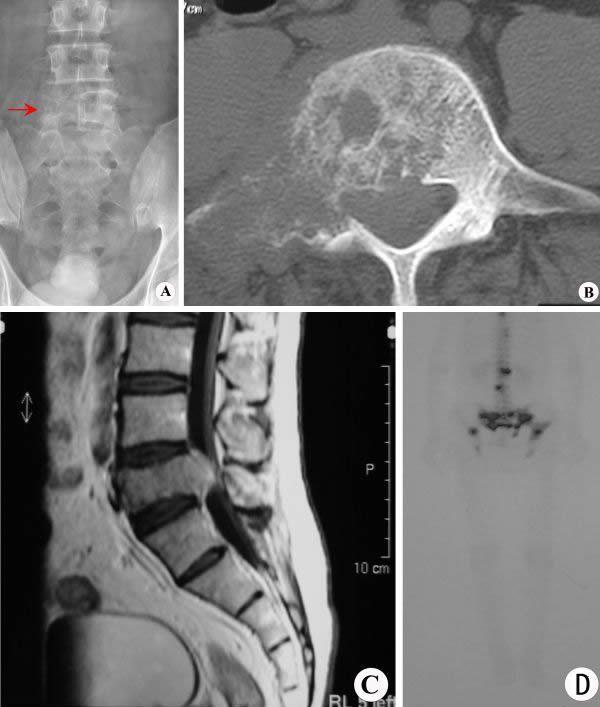

【影像表现】:腰椎X线正位(A)示腰5椎体变扁,右侧椎弓根及横突显示不清(↑);CT横断面(B)显示椎体、右侧椎弓根及横突骨质破坏,病灶边界模糊。MRI矢状面T1WI增强扫描(C)显示腰5椎体变扁,病变突入椎管内,并可见病变强化;核素显像(D)示脊椎及骨盆多发放射性浓聚。

【影像诊断】:骨转移瘤。